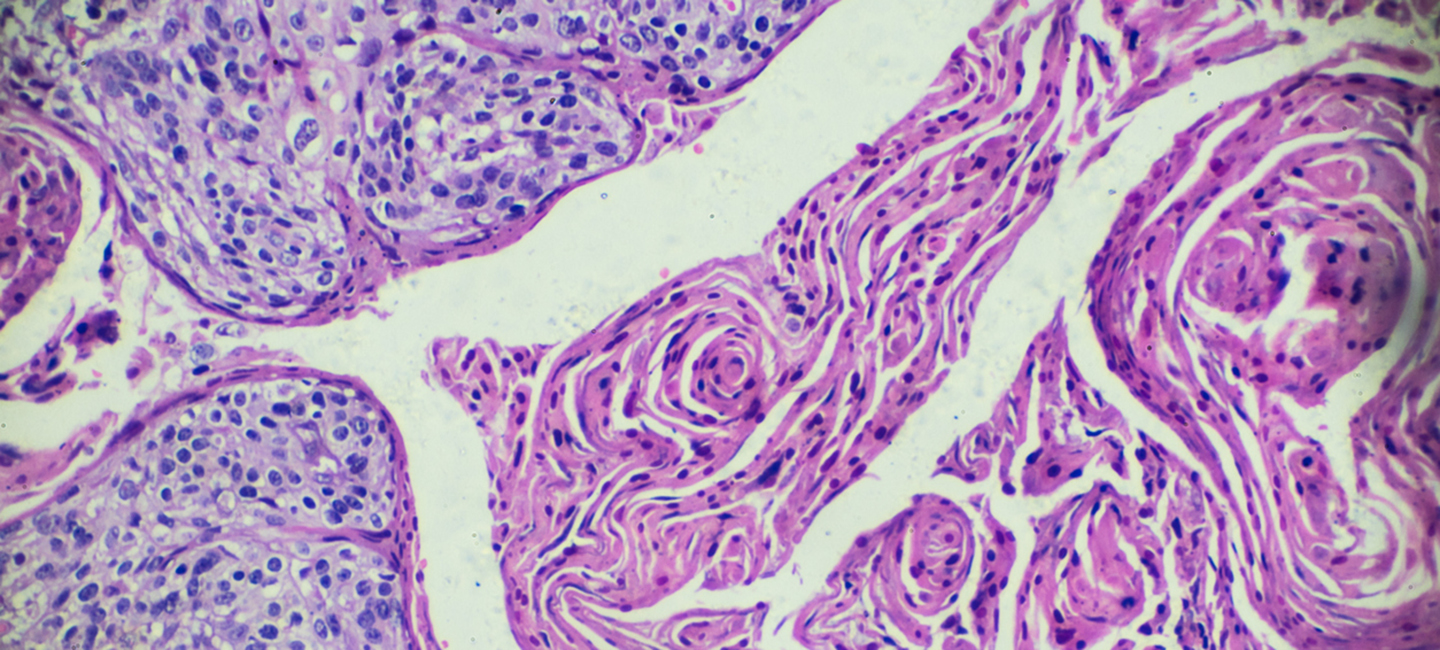

The numbers are encouraging, but Moffitt Cancer Center’s Dr. Anna Giuliano, founding director of the Center for Immunization and Infection in Cancer, says more can be done. “The vaccine protects against seven types of the HPV we know can cause cancer. We have the opportunity to prevent, and in some cases, eliminate HPV-related cancers, but we need more children and young adults to get vaccinated” she said.

Moffitt has partnered with more than a 70 cancer centers and health care organizations to endorse a call to action to eliminate HPV-related cancers, beginning with cervical cancer, through gender-neutral HPV vaccination and evidence-based cancer screening. “Our goal is complete vaccination of more than 80% of males and females ages 13 to 15,” Giuliano added.